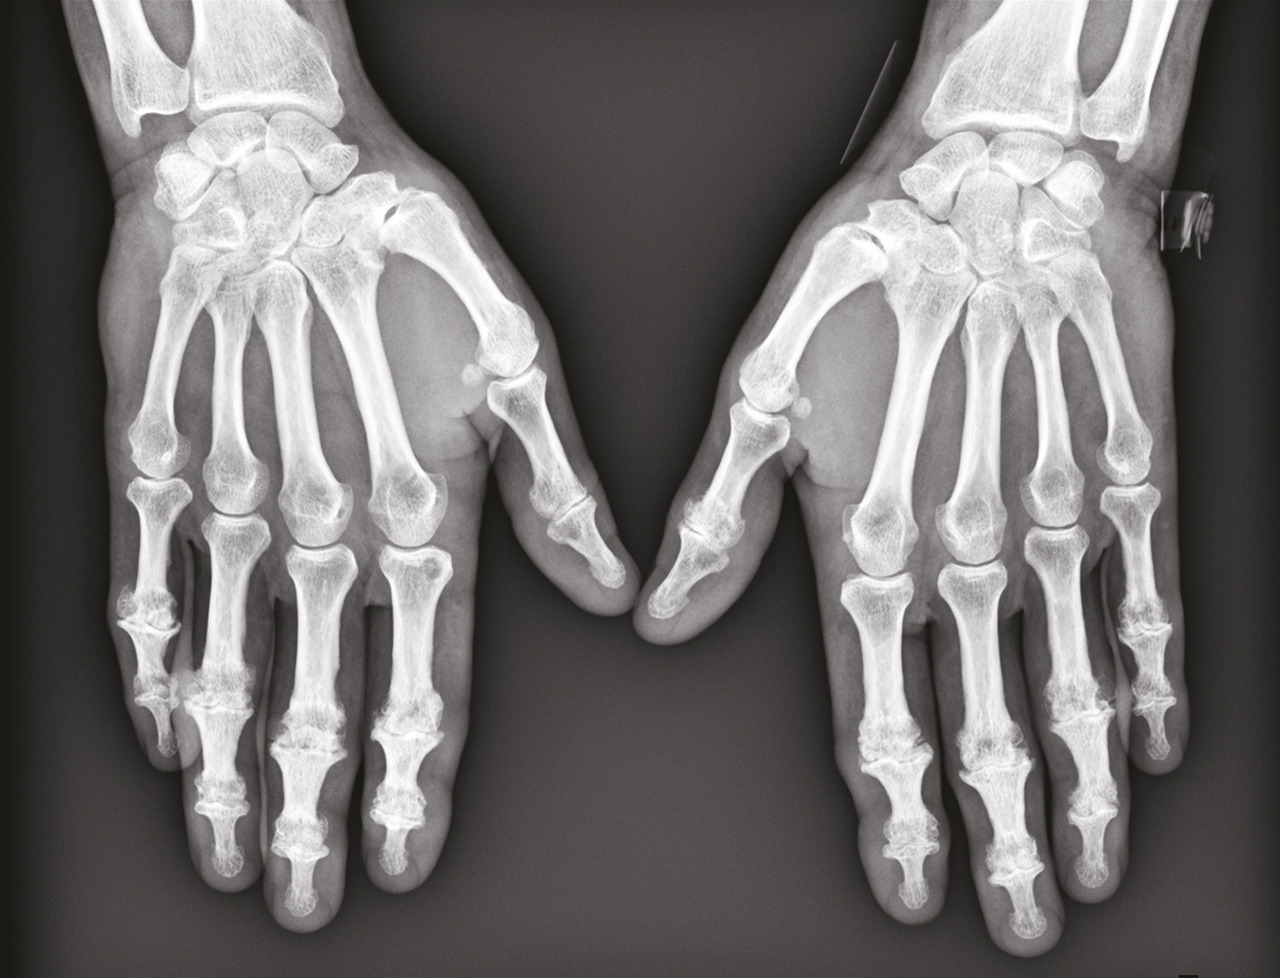

L’arthrose digitale des doigts longs évolue souvent par crises douloureuses et peut se distinguer par des signes inflammatoires locaux, en regard des articulations concernées, notamment dans sa forme érosive (figures). Un discret épanchement synovial peut être palpé, essentiellement au niveau des IPP, tandis que les kystes mucoïdes se développent surtout aux dépens des IPD. À un stade avancé, certaines articulations IPD sont le siège d’une laxité latérale, liée aux érosions osseuses et à la distension capsuloligamentaire. Des nodosités d’Heberden (IPD) et de Bouchard (IPP) peuvent être palpées : elles correspondent à l’ostéophytose du pourtour de l’articulation arthrosique. Une évolution vers l’ankylose des articulations distales est possible, à l’origine d’une déformation en position vicieuse et/ou d’un défaut de flexion, qui gênent considérablement la préhension.

La prévalence radiographique est supérieure à celle symptomatique

Dans la cohorte de Rotterdam (n = 3 906), la prévalence radiologique de l’arthrose digitale a été estimée chez les patients de plus de 55 ans : 67 % des femmes et 54,8 % des hommes inclus avaient au moins une articulation arthrosique. Les articulations les plus concernées étaient : les interphalangiennes distales (47,3 %), la trapézométacarpienne (35,8 %), les interphalangiennes proximales (18,2 %), puis les métacarpophalangiennes (8,2 %). Au cours de la vie, le risque de développer une arthrose digitale est de 47 % chez les femmes et de 24 % chez les hommes aux États-Unis.